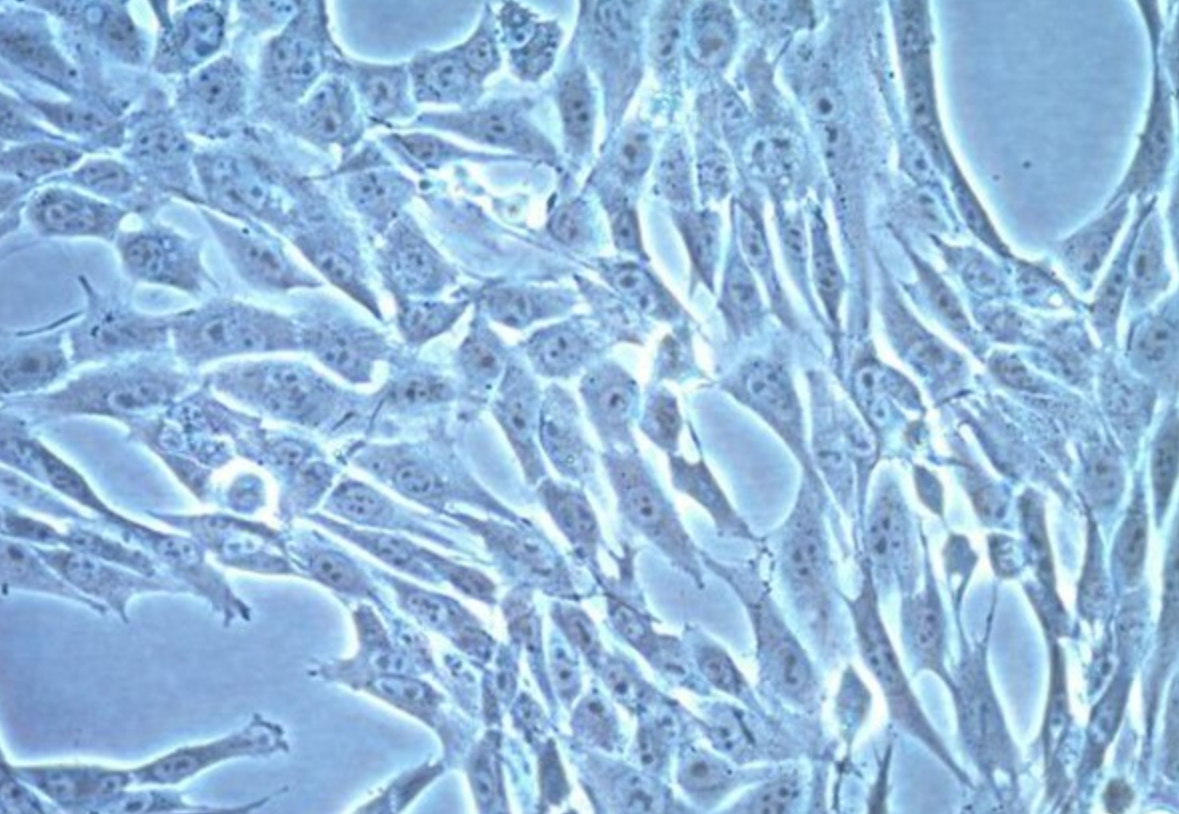

形態 |

上皮細胞樣 |

生長特征 |

貼壁生長 |